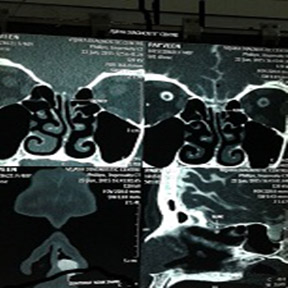

Fig 3: CT cisternography showing CSF leak

There was no previous history of accidental or Iatrogenic trauma or history of meningitis. She is a known case of diabetes and hypothyroidism and on medications. On examination she had deflected nasal septum towards right side and other E.N.T examination findings were within normal limits. Diabetic profile and thyroid profile were within normal limits. A CT Cisternography of Paranasal sinus was done (Fig. 3). The clear fluid collected on stooping was sent for glucose analysis (61mg/dl) and was suggestive of CSF.